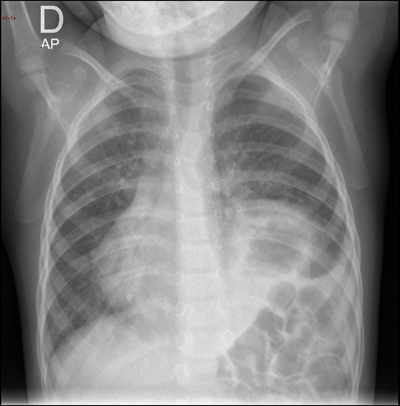

Tras el inicio de la antibioterapia, la paciente mejora rápidamente en menos de 48 horas. Usted, que regresa al hospital tras haber librado la guardia, consulta el informe del radiólogo en el ordenador.

Tras la sorpresa inicial, decide consultar de forma directa al especialista.